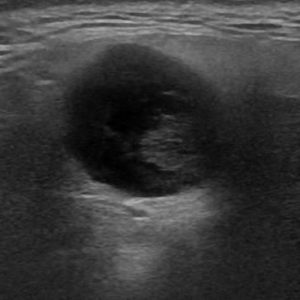

U tuyến nước bọt

Lượt xem: 138» 19-01-2021 -

U tuyến nước bọt

Lượt xem: 153» 19-01-2021 -

U tuyến nước bọt

Lượt xem: 131» 19-01-2021 -

U tuyến nước bọt

Lượt xem: 102» 19-01-2021 -

U tuyến nước bọt

Lượt xem: 146» 19-01-2021 -